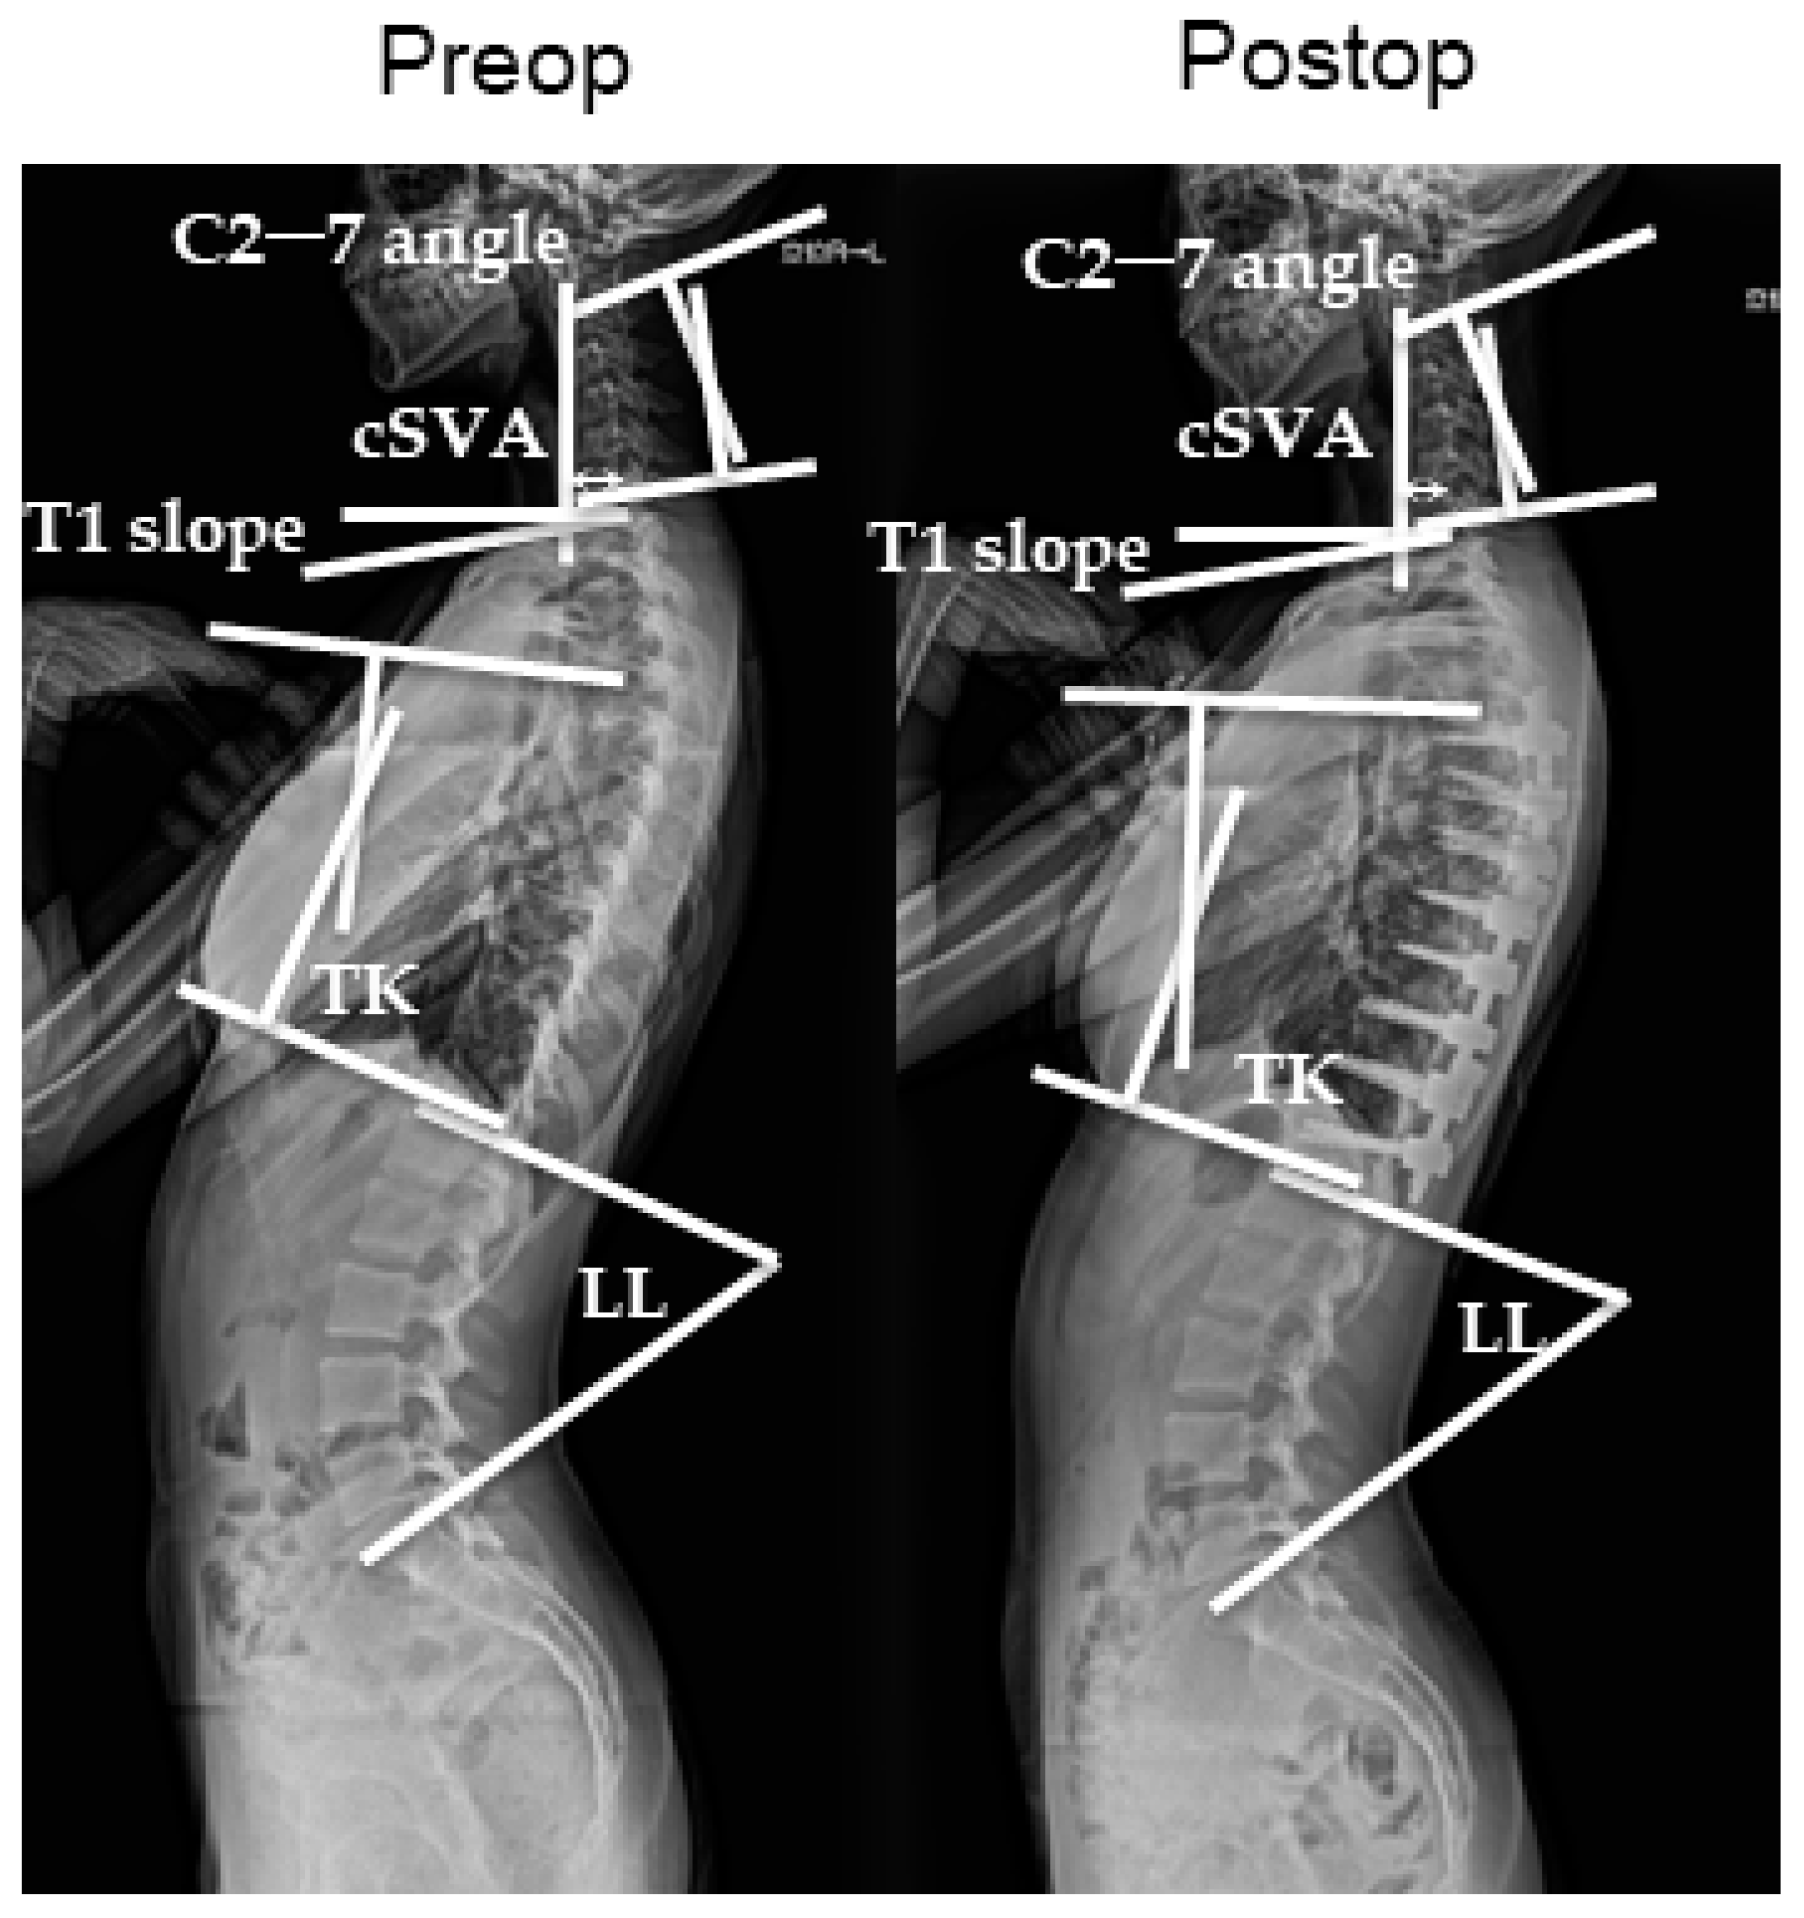

2.4. Radiographic Parameters

| C2–7 angle, ° | −1.99 ± 1.43 | 3.88 ± 2.24 | p < 0.005 * |

| C2–7 SVA, mm | 21.1 ± 1.71 | 20.9 ± 1.58 | p < 0.005 * |

| TK, ° | 21.2 ± 1.05 | 25.4 ± 1.77 | p < 0.005 * |

| T1 slop, ° | 17.9 ± 1.37 | 20.7 ± 1.06 | p < 0.005 * |

| LL, ° | 43.3 ± 1.64 | 43.6 ± 1.36 | NS |